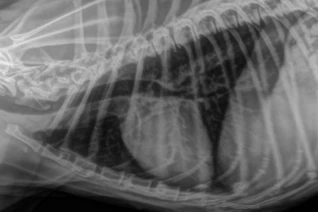

Radiografia torácica (padrão bronquial aumentado)